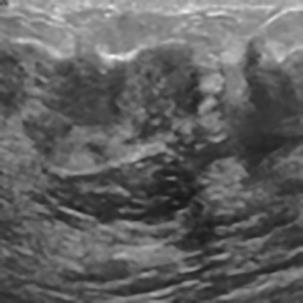

乳腺癌是全球女性最常见的恶性肿瘤之一,准确的病变分割对于乳腺癌的早期诊断与治疗具有重要意义。然而,由于病变形态的多样性以及超声成像机制的复杂性,现有基于深度学习的乳腺超声图像病变分割方法在分割准确性方面仍面临巨大挑战。为进一步提升乳腺超声图像中病变区域的分割精度,该文基于经典U-Net架构,提出了一种新型乳腺超声图像病变分割网络(CWSASKM-BBAM-Net)。首先,在网络中引入逐通道空间自适应选择核卷积模块(CWSASKM),根据不同通道的语义特征为每个空间位置自适应选择感受野大小,以增强多尺度信息的建模能力;然后,引入双向边界感知机制(BBAM),通过融合正向与反向注意力,对目标显著区域及其边界进行协同建模,同时逐步提升对非显著区域与病变区域的区分能力,以进一步强化边界信息的表达;最后,在3组公开乳腺超声图像数据集(BUSI、UDIAT和STU)上开展分割实验。结果表明:该方法在数据集BUSI上的杰卡德指数、精确率、召回率和Dice相似系数分别为71.97%、82.85%、81.40%和80.44%,较次优方法分别提升1.69、1.05、1.28和1.84个百分点;在数据集UDIAT上,这4项指标分别达到78.14%、88.31%、86.73%和86.10%,较次优方法分别提升了2.75、2.04、0.56和2.01个百分点;在外部数据集STU上,该方法也取得了优于其他方法的整体表现。实验结果表明,CWSASKM-BBAM-Net在乳腺超声图像分割任务中展现出更优的整体性能。